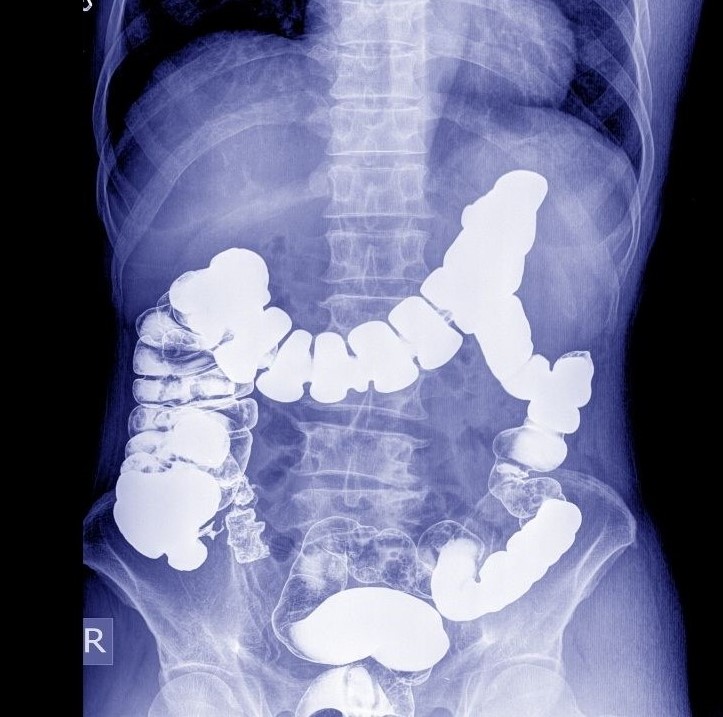

رادیولوژی